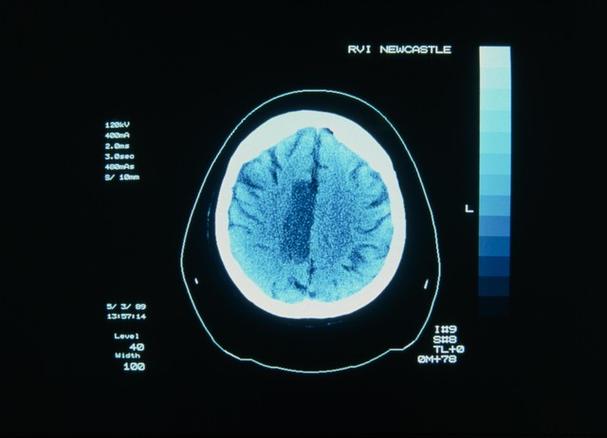

- 本质:是一种疾病,医学上称为“缺血性脑卒中”。

- 病因:供应大脑血液的血管被堵塞了,导致大脑某个区域因为缺血缺氧而坏死、软化,就像一个城市的供水管道突然被堵住了,导致部分区域断水。

- 位置:大脑内部。

这是两者最关键的联系。脑梗是“因”,呛咳是“果”,当脑梗发生后,特别是发生在某些特定部位时,会直接导致吞咽功能障碍,从而引发呛咳。

脑梗影响吞咽功能的原因有:

损伤吞咽神经中枢:

- 大脑中负责管理吞咽动作的神经中枢(位于脑干)受损,导致吞咽肌肉(如咽喉部肌肉)不协调、无力或麻痹。

- 结果:食物和口水无法准确进入食道,而是“走错路”进入了气管,引起呛咳,这在医学上称为“吞咽困难”。